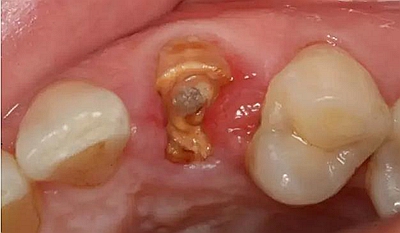

患者女性,55歲,3年前B3纖維樁+鑄瓷全冠修復,一周前牙冠折斷,就診后,發(fā)現纖維樁根管口處折斷,周圍牙齦增生,建議患者行冠延長手術。首先去除斷端的纖維樁。拍片示牙根長度充足。于是開始冠延長手術。

因為是前牙,故該患者將來修復體邊緣必須為齦下,所以3個月后再行修復。以下為手術前照片。

以下為術中照片。

內斜切口,頸圈組織,改良垂直褥式縫合。